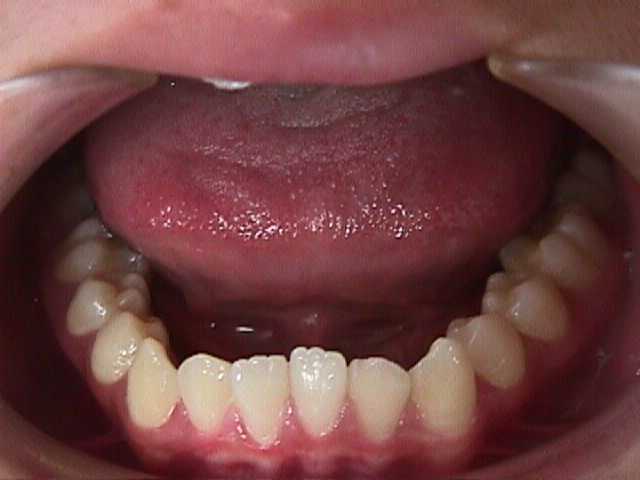

【矯正症例】左上2番3番逆転症例2

Before

After

左上2番3番逆転症例

随分、前の症例で現在、写真しか残っておりません。

治療費や、治療期間を掲載できないことをご了承ください。

私の矯正歯科医の人生の中でも、特に思い出深い症例です。